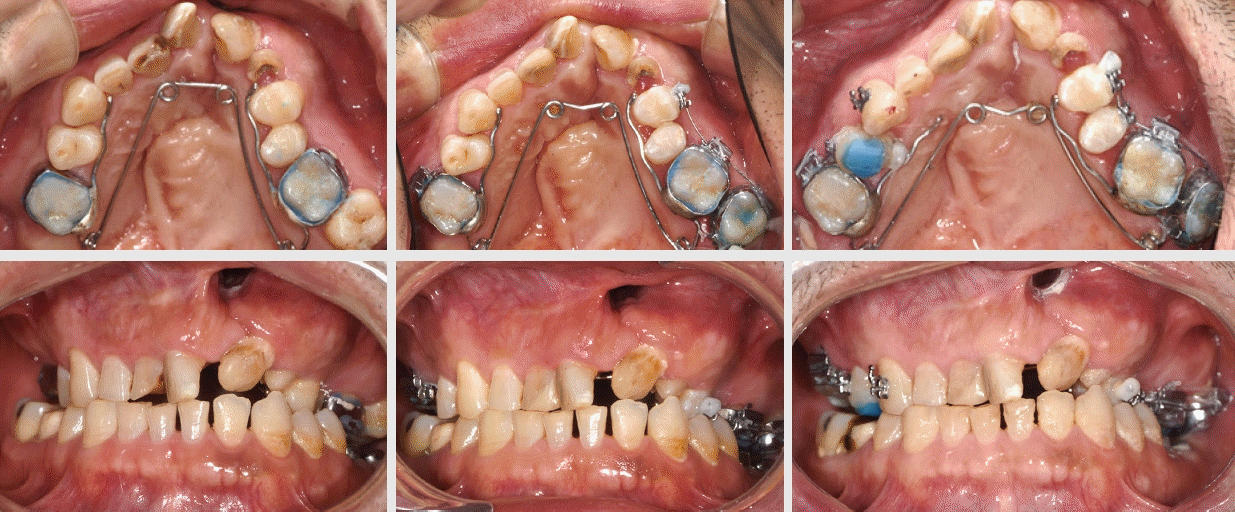

Figure 7.

Upper row: pre-surgical axial view, bone graft, and intra-oral photo

Lower row: 3 month follow-up axial view with new bone bridge, archform, and frontal view.